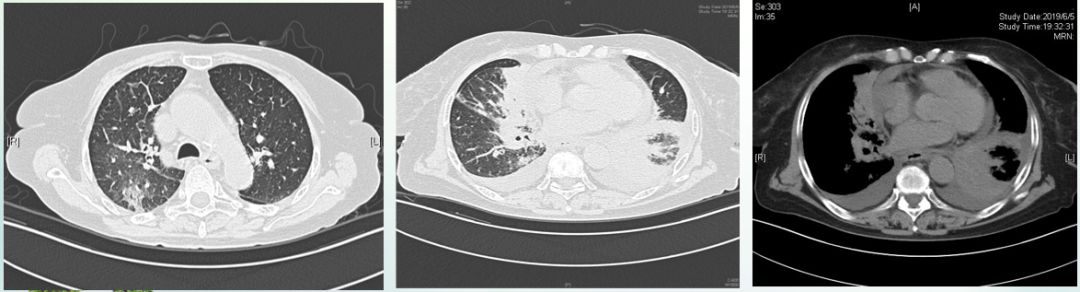

入我院后完善检查,CT可见双肺多发磨玻璃、斑片状阴影,右中叶、左下叶大片实变,双侧少量胸水,心包积液。

病理结果提示为浸润性腺癌。进行PET-CT检查也提示左肺下叶支气管分支闭塞伴肺叶实变、代谢增高,全身多发淋巴结肿大伴代谢增高,考虑为来源于肺恶性肿瘤伴全身多发转移;两肺间质增粗模糊伴高代谢,癌性淋巴管炎可能;双侧胸腔积液伴两肺膨胀不全、心包积液、盆腔积液少量腹腔积液。最终确定诊断为双侧肺腺癌IV期(T4N3M1c)。